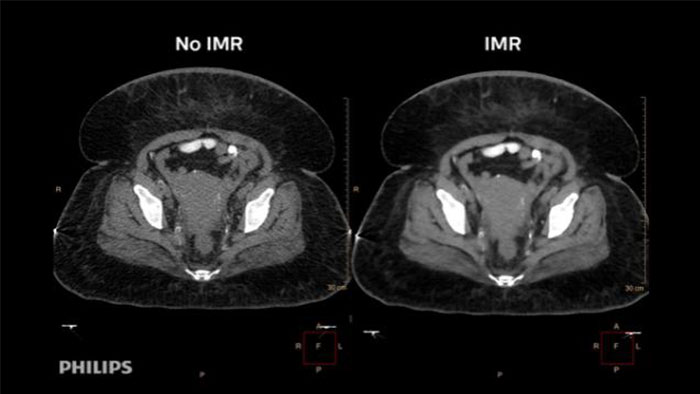

“By using Philips’ advanced imaging techniques like 3D, MIP, and MPR, we can easily bring up images and manipulate them to fine-tune our diagnoses. We get a better idea of the extent of the disease and can make better recommendations to the clinician about what’s going on.” Dr. D’Arcy Little

MD, CCFP, FRCP, Radiologist, Orillia Soldiers’ Memorial Hospital, Orillia, Ontario